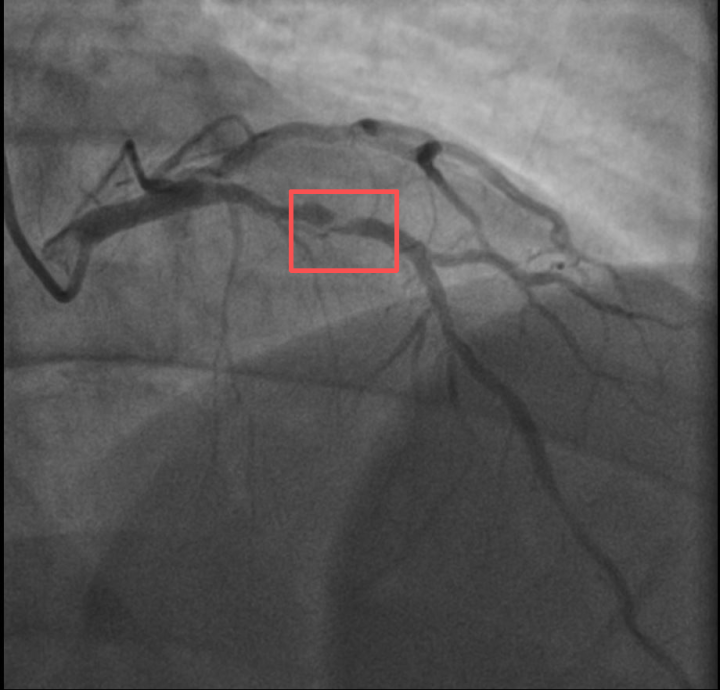

介入治疗前影像图

孙先生(化名)身高173cm,体重约90KG,是一位羽毛球教练。一年前,他因胸闷就诊时被查出心脏右冠中段、远端钙化斑块,以及心脏三支主要血管之一前降支中段60%狭窄。

医生分析,剧烈运动导致孙先生心脏的不稳定斑块破裂,进而造成前降支近段次全闭塞。所幸送医及时,孙先生的身体险情被化解。